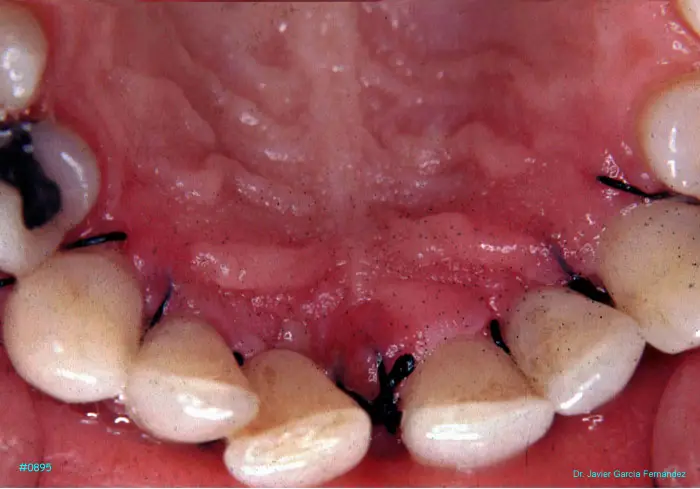

Atlas of Surgical Techniques in Periodontics. Chapter III. Atlas de Técnicas Quirúrgicas en Periodoncia